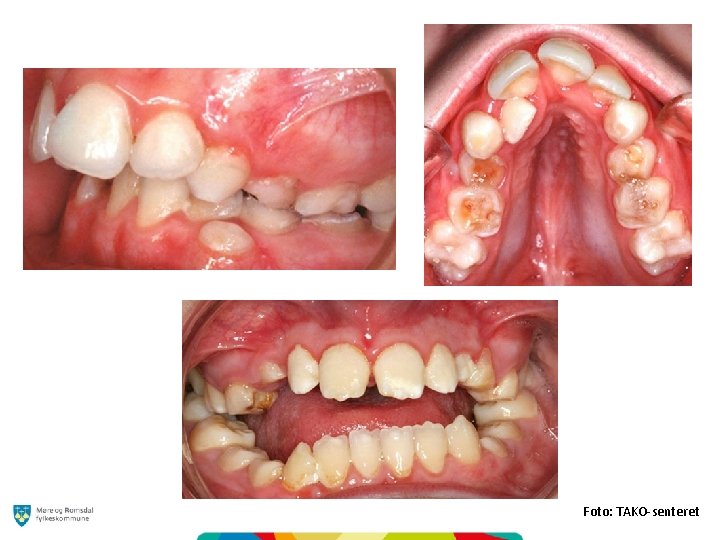

Kjennetegn og utfordringer ved enkelte syndromer og tilstander Foto: TAKO-senteret

Utfordringer ved enkelte syndrom Foto: Frambu

Foto: TAKO-senteret